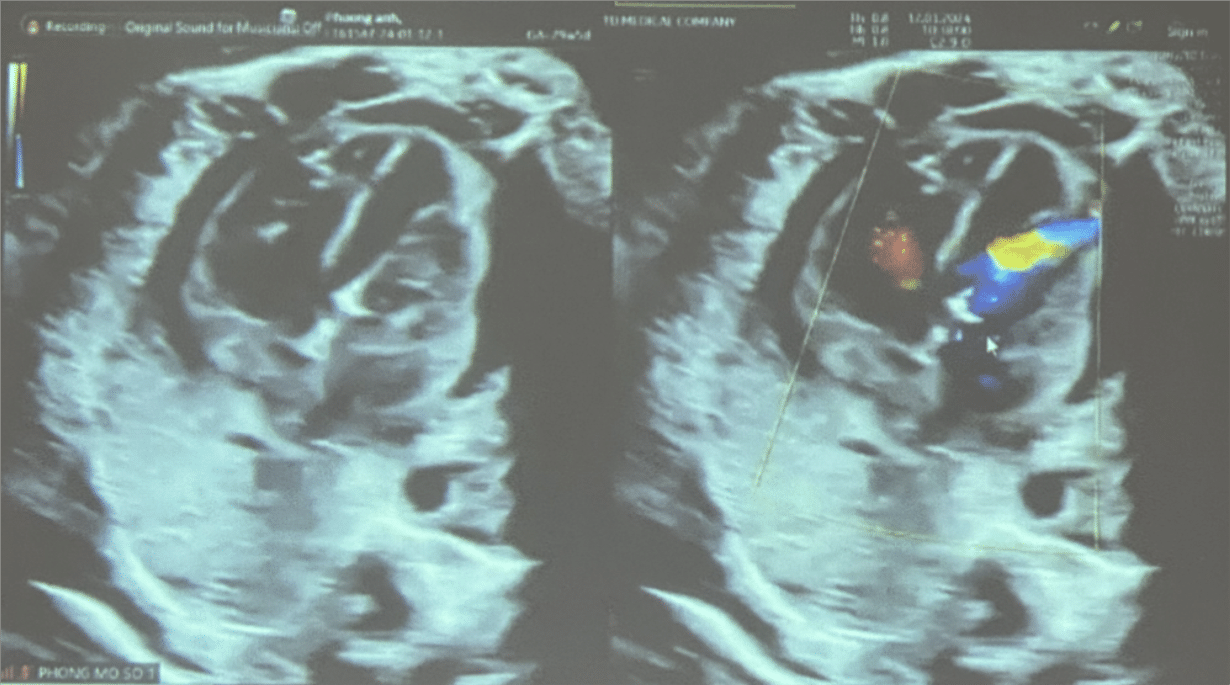

Thêm một ca thông tim can thiệp xuyên tử cung cứu bào thai

7 ngày sau ca thông tim can thiệp bào thai đầu tiên thành công tại Việt Nam, thêm một bào thai 29 tuần tuổi được thông van tim thành công trong bụng mẹ.